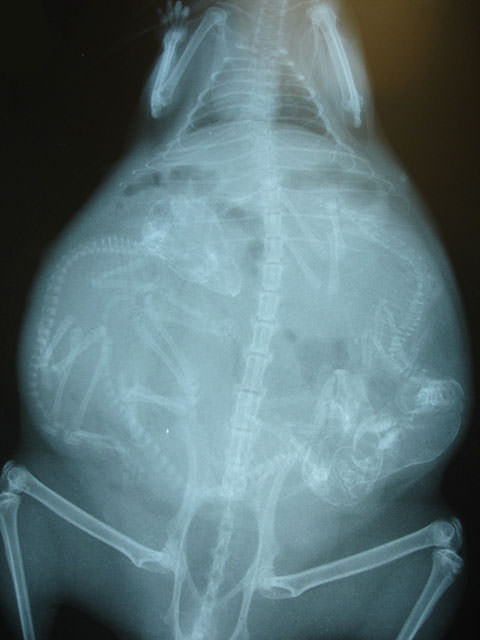

İnsanların ultrason görüntülerini görmeye hepimiz alışkınız. Ancak hamile hayvanların ultrason görüntüleri sizleri çok şaşırtacak.Kaplumbağa

İnsanların ultrason görüntülerini görmeye hepimiz alışkınız. Ancak hamile hayvanların ultrason görüntüleri sizleri çok şaşırtacak.